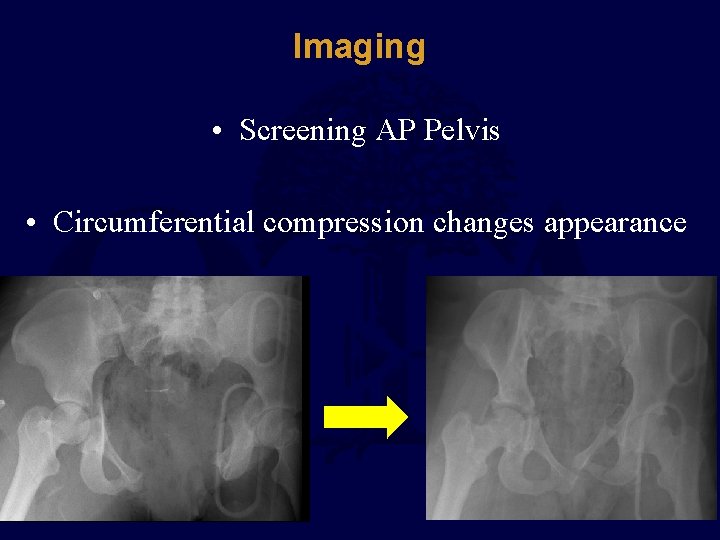

Imaging • Screening AP Pelvis • Circumferential compression changes appearance